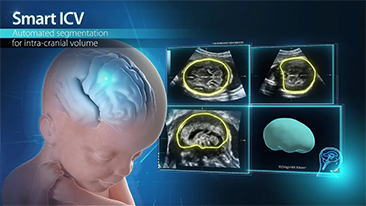

Geli?mi? ZST+ platformu ile desteklenen Nuewa'n?n tam kapsaml? ak?ll? ??zĂŒmleri, ?zellikle gebelik ?ncesi, gebelik ve do?um sonras? iyile?me sĂŒre?lerinde kad?n sa?l???n? iyile?tirmek, seviyeleri giderek daha da artan klinik zorluklar?n ĂŒstesinden gelmek i?in kapsaml? ve verimli tan?lar sunmak ĂŒzere tasarlanm??t?r.